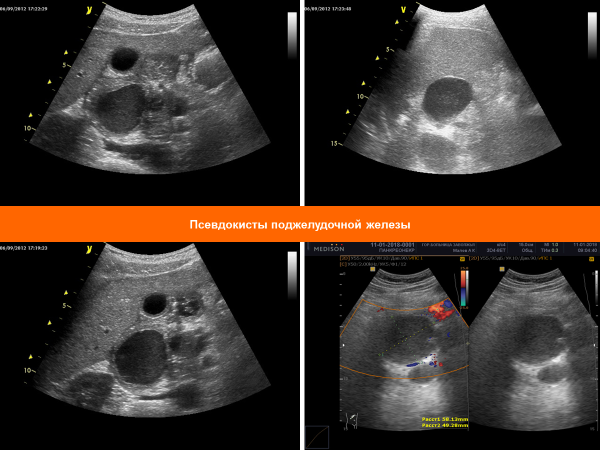

Ложные кисты (псевдокисты) поджелудочной железы

Инкапсулированные фиброзной тканью скопления секрета поджелудочной железы и воспалительного экссудата без эпителиальной выстилки. Ограничены

окружающими тканями и органами с формированием фиброзной псевдокапсулы и, в отличие от истинных кист, не имеют эпителиальной выстилки. Составляют 90% всех кистозных образований поджелудочной железы. Псевдокисты могут персистировать, разрешаться или увеличиваться в размерах. Спонтанное разрешение псевдокист наступает в 25-40% случаев.

При УЗИ: Обычно четко отграниченное гладкостенное однокамерное перипанкреатическое анэхогенное аваскулярное образование с дорсальным псевдоусилением сигнала. Могут быть осложненные псевдокисты (приблизительно 6% случаев) - многокамерные гетерогенные неоднородной структуры кистозные образования, имеющие в просвете уровень жидкость/детрит, различные включения, газ и перегородки (вследствие кровоизлияния/ инфекции), фиброз/кальциноз стенки. Может быть смещение прилежащих органов и сосудов.

Могут быть экстрапанкреатические (околоселезеночные, забрюшинные, внутрибрюшинные и медиастинальные) и интрапаренхимальные (левая доля печени, селезенка, почки) псевдокисты.

Могут быть осложненные псевдокисты (приблизительно 6% случаев) - многокамерные гетерогенные неоднородной структуры кистозные образования, имеющие в просвете уровень жидкость/детрит, различные включения, газ и перегородки (вследствие кровоизлияния/ инфекции), фиброз/кальциноз стенки.